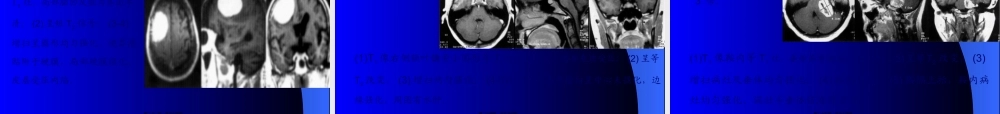

延髓颈髓蛛网膜下腔左侧椎动脉硬膜外脂肪第一页,共三十五页。女39岁,双上肢麻木,肉跳手变细2年。双上肢肌萎缩,肌力III-IV,颈5以下痛觉减低。T1小脑扁桃体及延髓下疝至颈椎管内颈3-胸4脊髓中央管扩张;FLASH(500/45/35)枕大池颅内外段消失,延髓中央管闭塞,颈1-2后纵韧带增厚钙化第二页,共三十五页。男55岁,左顶受击后头痛半月,以左侧面为主,无呕吐。体征:左侧面部角觉敏感。T1(360/11)左侧顶叶颅板下类梭形短T1病灶,皮质受压,脑室系统无改变,T2(2200/120)上述病灶呈长、短混杂改变。第三页,共三十五页。男59岁,急起双下肢无力三天,1月前有轻微头部外伤史。伸舌偏右,双下肢肌力IV,左侧上肢张力增高,左侧巴氏征(+)。T1(360/11)两侧额叶脑外大片长梭形短T1病灶,局部皮质受压,大脑纵短T1病灶;T2(2200/120)上述病灶呈长T2及混杂T2改变;T1(320/15)上述病灶呈短T1,两侧脑室、前角受压,变形,下移。第四页,共三十五页。女58岁,反复头痛伴双眼视力下降1年,左肢体无力三天。左侧中枢性面瘫,左上肢肌力III-IV。(1,2)T1(360/11)右侧额叶顶见大片低信号,脑组织介面不清;(3,4)T2(3300/120)上述病灶呈长T2信号;(5,6)增强T1(320/15)上述病灶呈不规那么脑回样、片状强化。第五页,共三十五页。男43岁,急起右侧肢体无力,言语不清1小时。神志清,右侧肢体肌力IV。(1,2)T1(360/11)左侧额顶颞叶顶见大片稍长T1信号,其间有小块状T1改变,占位效应显著,右侧脑室体旁小点状长T1信号;(3,4)T2(2200/120)上述病灶呈长T2信号,累及皮层。第六页,共三十五页。男58岁,急性头痛,言语不清2天。1年来反复发作;失语,伸舌偏右,右半身肌力差。(1,2)T1左颞枕叶大片长T1信号,左侧基底节点状长T1信号;信号;(3,4,5)T2像上述病灶呈长T2信号;诊断:左颞枕叶脑堵塞(陈旧性);左侧基底区腔隙性脑堵塞(病灶新)。第八页,共三十五页。男57岁,急起右侧肢体乏力伴意识不清12天。睁眼昏迷,右侧肢体肌力0。(1)T1左侧大脑半球有大片长T1信号,其中可见斑点状短T1信号,左侧面脑室轻度受压;(2)T2像上述病灶呈混杂T2信号;由于位于左大脑动脉分布区,堵塞后出血多为瘀斑状,无血肿中心,含铁血黄素沉着呈不规那么的点状。第九页,共三十五页。女69岁,渐起发呆半月,3天前言语不清、吞咽困难。神志欠清,右侧上下肢肌力差,病理反射(+)。(1,2)T1左侧颞叶有斑点状短T1信号及右侧基底区境界不清的稍长T1信号;(2)T2像上述病灶呈长T2信号;第十页...